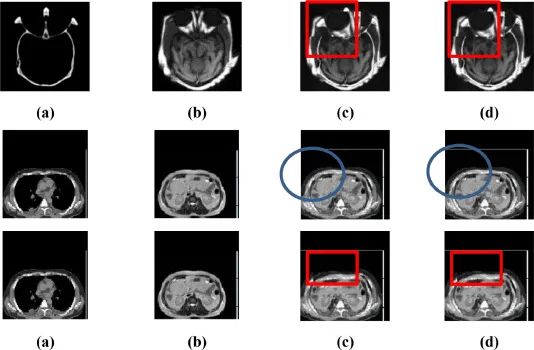

深度學習研究眼下大多集中在單圖像融合,很少將其用于多圖像分批處理。青島大學數據科學與軟件工程學院的研究人員開發出一種基于深度學習的多模態醫學圖像融合方法。它不僅可以彌補MRI、CT和SPECT圖像融合的不足,而且可以在不同類型的多模態醫學圖像融合問題中實現批處理。該方法大大提高了MRI、CT和SPECT圖像融合效果和細節清晰度。這項研究成果發表于2021年6月的International Journal of Cognitive Computing in Engineering雜志上。

從紅色標定框圈出的區域可以看出,融合結果清晰,邊緣清晰,對比度明顯,能夠反映圖像中的關鍵信息,有效去除虛影(virtual shadow)。而且融合圖像中包所含的信息已經覆蓋了CT和MRI、MRI和SPECT兩種多模態圖像中的大部分信息,可以有效補充單一MRI/CT/SPECT圖像信息的不足。

同時,文章中也指出,REL和STD方面稍遜一籌,說明融合過程會造成信息的丟失,如何學習模型參數、增加訓練數據的規模、提高訓練的準確率是需要進一步研究的問題。